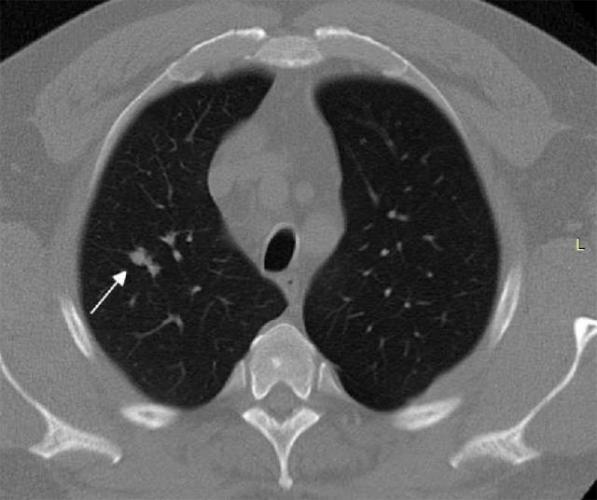

- Очаговые образования представляют собой участки белого цвета на черном фоне (на снимке-негативе). В реальности пораженная область, скорее всего, имеет более темный цвет, чем здоровые ткани легкого.

- Если врач заметит на снимке участки кальцинирования или обызвествления (капсул, пропитанных солями кальция) вокруг очага, это может быть признаком доброкачественности образования. Кальцинаты по цвету похожи на кости скелета, видимые на этом снимке. Такие явления часто обнаруживаются после затяжных простудных заболеваний, бронхитов или уже излечененного туберкулеза и представляют собой некий шрам на легких. Пациента с образованием, на котором заметны признаки кальцината, пульмонологи обычно просят раз в полгода делать контрольные снимки.

- В случае, когда образование представляет собой так называемое «облачко» или очаг по типу «матового стекла», требуется более предметное обследование. Внешне оно выглядит как затуманенная область с размытыми границами. В ряде стран пациентам с такими образованиями сразу рекомендуется операция, даже если оно не растет. Уже доказано, что в 80% случаев такие очаги являются предраковым состоянием легких. Альтернатива немедленной операции — постоянное наблюдение с контрольными снимками раз в полгода-год.